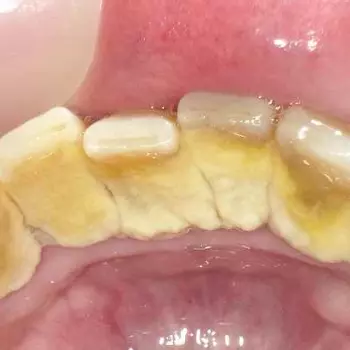

치석은 이름처럼 돌처럼 단단하므로 일반 칫솔질로는 제거가 불가능하며, 치석을 제때 제대로 제거하지 않으면 증상이 악화되어 치은염이나 치주염으로 발전될 수 있으니 적절히 케어해야 합니다.

구강 내의 세균과 인산, 칼슘, 음식물 찌꺼기 등의 결합물인 치석은 플라크와 결합하여 치아 표면의 치석 형성을 촉진시킵니다.

올바르지 못한 칫솔질 방법과 탄산음료와 같은 과도한 당의 섭취, 고르지 않은 치아 배열은 치석 형성을 촉진할 수 있으며, 치주 질환이나 구강 건강에 문제가 있을 경우에는 치석이 더 쉽게 발생할 수 있습니다.